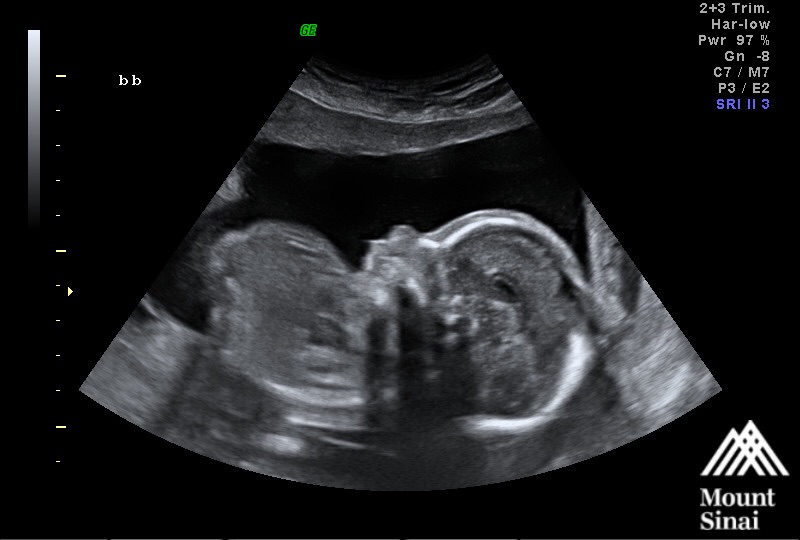

The baby is much cuter than seeing me right now. I fall more in love when I see him. Did my fetal Echo and advanced a/s and things are looking good for him